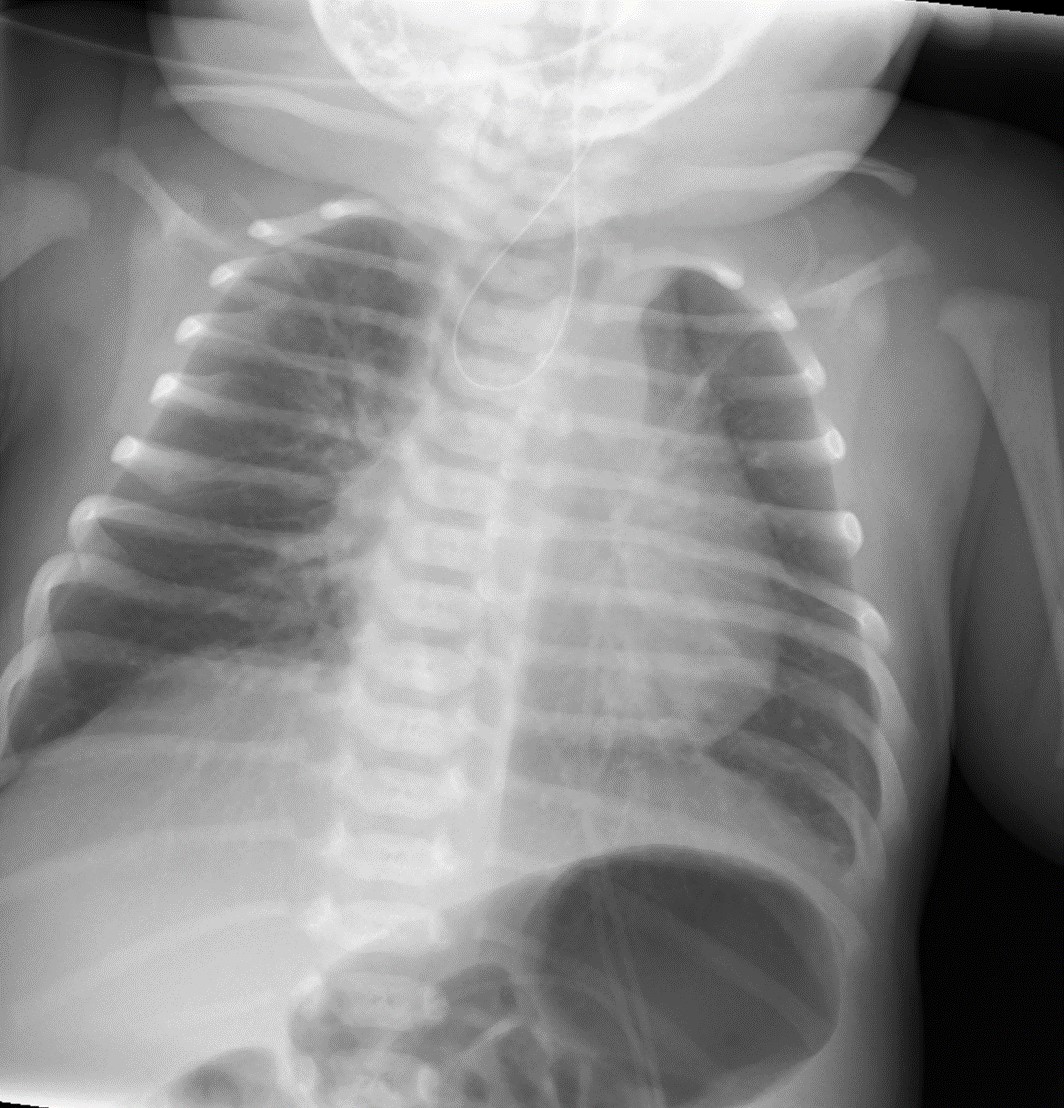

Recién nacido a término con embarazo normoevolutivo, sin hallazgos significativos en las ecografías prenatales y parto sin complicaciones. Avisan a las 7 horas de vida por abundantes secreciones orofaríngeas y dificultad respiratoria. A la exploración se objetiva abundante sialorrea, auscultándose ruidos de secreciones de vías altas. Se aspiran las secreciones, se inicia oxigenoterapia de alto flujo y se coloca sonda orogástrica con imposibilidad de avance. Se solicita una radiografía de tórax (Figura 1).